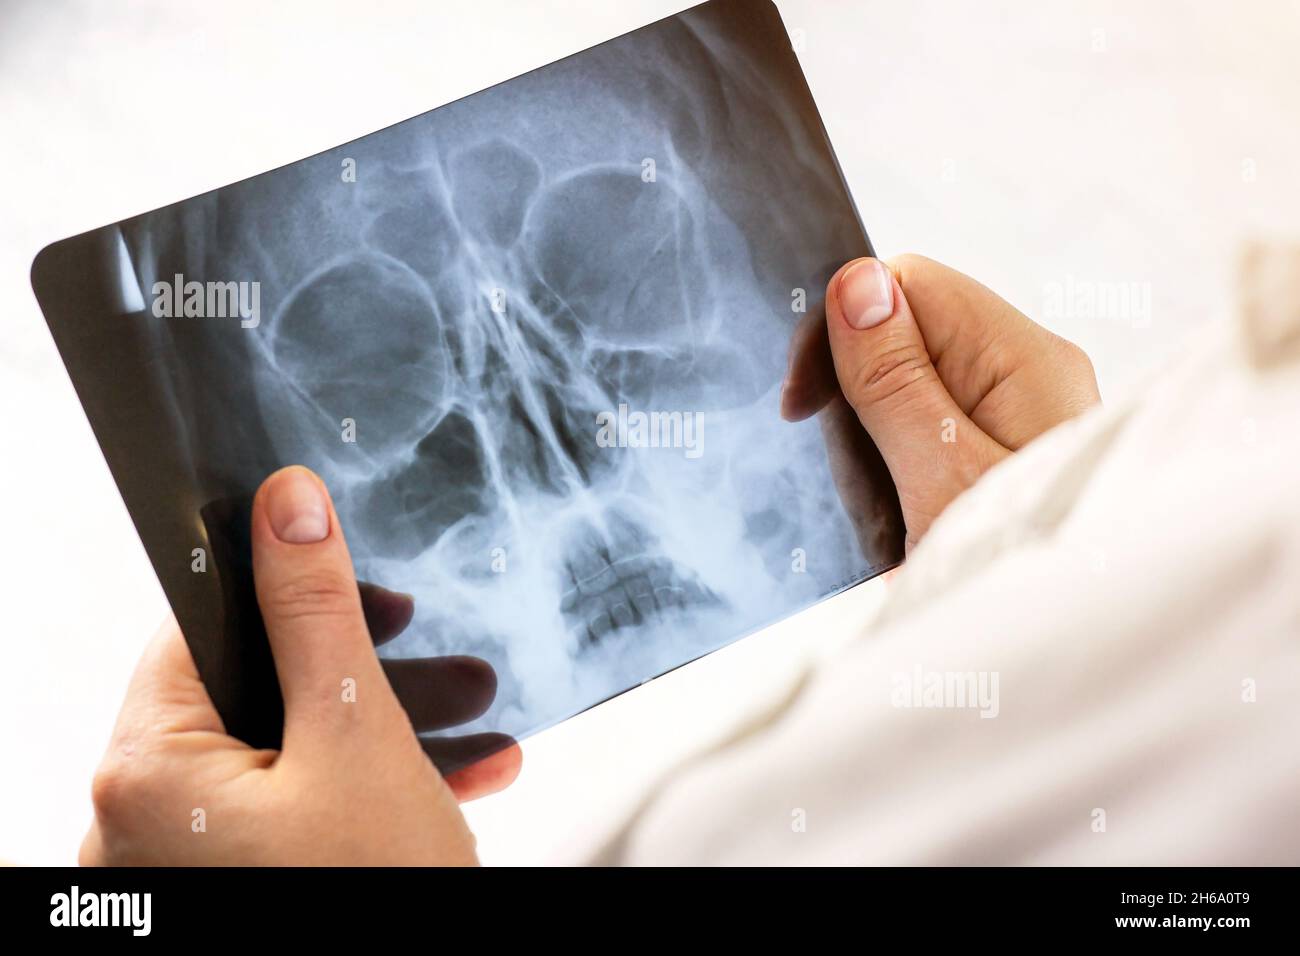

Acquisition par résonance magnétique d'un cerveau humain avec crâne dans les mains du médecin.Examen de la tête par IRM sur fond clair dans un hôpital.Recherche de rayons X pour la défacilité o Banque D'Imageshttps://www.alamyimages.fr/image-license-details/?v=1https://www.alamyimages.fr/acquisition-par-resonance-magnetique-d-un-cerveau-humain-avec-crane-dans-les-mains-du-medecin-examen-de-la-tete-par-irm-sur-fond-clair-dans-un-hopital-recherche-de-rayons-x-pour-la-defacilite-o-image451377705.html

Acquisition par résonance magnétique d'un cerveau humain avec crâne dans les mains du médecin.Examen de la tête par IRM sur fond clair dans un hôpital.Recherche de rayons X pour la défacilité o Banque D'Imageshttps://www.alamyimages.fr/image-license-details/?v=1https://www.alamyimages.fr/acquisition-par-resonance-magnetique-d-un-cerveau-humain-avec-crane-dans-les-mains-du-medecin-examen-de-la-tete-par-irm-sur-fond-clair-dans-un-hopital-recherche-de-rayons-x-pour-la-defacilite-o-image451377705.htmlRF2H6A0T9–Acquisition par résonance magnétique d'un cerveau humain avec crâne dans les mains du médecin.Examen de la tête par IRM sur fond clair dans un hôpital.Recherche de rayons X pour la défacilité o